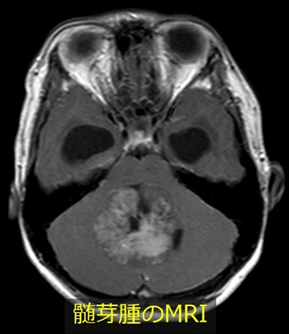

小児における代表的な脳腫瘍であり、ほとんどが小脳に発生します。ふらつきなどの小脳失調に加えて水頭症による頭蓋内圧亢進症状が現れることがあります。

以前は治癒困難な脳腫瘍でしたが、手術手技の向上や放射線治療・化学療法の進歩によって治療成績は確実に向上しています。手術でできる限り腫瘍を摘出し、全脳全脊髄への放射線照射と化学療法を追加することが標準治療となっています。